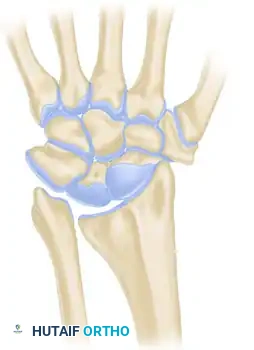

Léri-Weill dyschondrosteosis is a pseudoautosomal dominant skeletal dysplasia classically associated with mutations or deletions in the SHOX gene. Clinically, it manifests as mesomelic short stature and the characteristic Madelung deformity of the wrist. The hallmark of this deformity is a premature growth arrest of the volar-ulnar aspect of the distal radial physis, leading to an increased volar tilt, increased radial inclination, and secondary dorsal subluxation of the distal ulna.

A critical pathoanatomic feature of this condition is the presence of the Vickers ligament—an abnormally thickened, short, and hypertrophic radiolunate ligament. This aberrant ligament creates a dense fibrous tether between the volar-ulnar metaphysis of the radius and the lunate, compressing the volar-ulnar physis and exacerbating the asymmetric growth arrest.

Understanding the biomechanical forces at play is essential for executing this procedure successfully. The normal distal radius physis grows symmetrically, maintaining a neutral to slight volar tilt and a standard radial inclination. In dyschondrosteosis, the Vickers ligament acts as a rigid volar-ulnar tether.

* Carpal Subsidence: The lunate, tethered by the Vickers ligament, subsides proximally into the widened radioulnar space, creating a V-shaped carpal configuration.